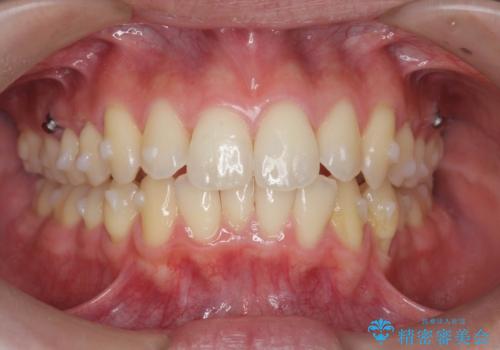

過蓋咬合・上顎前突・叢生を改善するマウスピース矯正

・前歯の深い噛み合わせ (過蓋咬合)

・上顎前突(Angle Class2)

・叢生(がたつき)

以上のような問題点をマウスピース矯正インビザラインとマイクロインプラントを用いて矯正治療を行い改善して行きます。

20時間以上のマウスピース装着、ゴムかけを遵守していただいたおかげでしっかりと噛み合わせ、がたつきの改善を行うことができました。